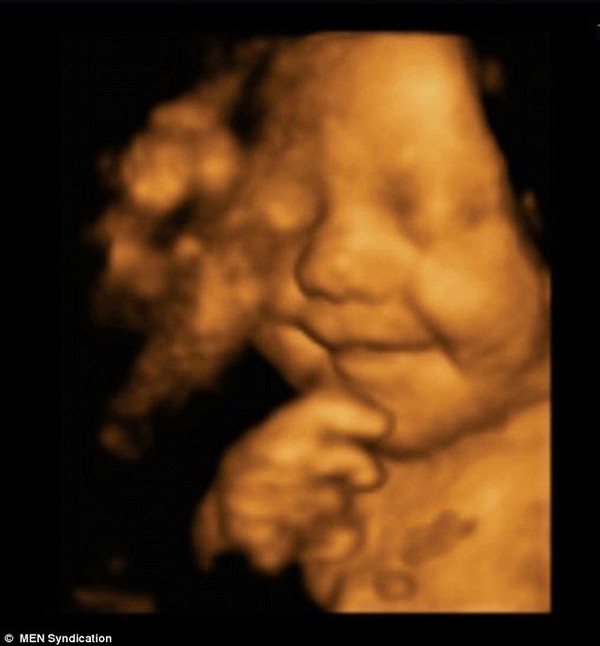

"Cậu bé hạnh phúc nhất nước Anh" biết cười khi còn trong bụng mẹ , Theo Mask Online 00:01 15/11/2014 Chia sẻ Theo dõi Kenh14.vn trên logo

Leo Hargreaves được nhận xét là "đứa trẻ hạnh phúc nhất Anh Quốc" bởi ngay từ trong bụng mẹ cho đến khi 5 tháng tuổi cậu bé luôn khiến người thân ấm áp bởi nụ cười vô cùng đáng yêu.

Ngay từ khi còn trong bụng mẹ, Leo Hargreaves đã khiến cha mẹ kinh ngạc tột cùng khi biết tạo dáng và mỉm cười vô cùng chuyên nghiệp. Hình ảnh siêu âm 4D cho thấy Leo mỉm cười trong bụng mẹ được các bác sĩ chụp lại khi mẹ cậu bé, cô Amy Cregg (24 tuổi, đến từ Accrington, Lancashire) đi khám thai lúc cô mang thai được 31 tuần. "Cậu bé hạnh phúc nhất nước Anh" biết cười khi còn trong bụng mẹ 1Leo mỉm cười cực đáng yêu trong bụng mẹ."Cả tôi và chồng đều rất kinh ngạc, thậm chí những bác sĩ siêu âm cho tôi cũng thế. Nhưng đó chỉ là bắt đầu. Sau khi chào đời, con luôn mỉm cười, kể cả khi đang ngủ", cô Amy chia sẻ.Hiện, Leo đã 5 tháng tuổi và cậu bé được bình chọn là "đứa trẻ hạnh phúc nhất Anh Quốc"."Cậu bé hạnh phúc nhất nước Anh" biết cười khi còn trong bụng mẹ 2Leo luôn mỉm cười, kể cả trong lúc ngủ."Cậu bé hạnh phúc nhất nước Anh" biết cười khi còn trong bụng mẹ 3Gương mặt xinh yêu của "cậu bé hạnh phúc nhất Anh Quốc".Với nụ cười cực đáng yêu, Leo trở nên khá nổi tiếng. Mẹ Leo cho biết đã từng có nhiếp ảnh gia tới nhà và đề nghị được chụp hình Leo khi cậu bé lớn hơn.(Nguồn: Dailymail) Theo Mask Online Copy link Link bài gốc Lấy link http://www.dailymail.co.uk/health/article-2834472/Is-happiest-baby-seen-womb-Heartwarming-scan-shows-baby-Leo-smiling-born.html TIN CÙNG CHUYÊN MỤC Xem theo ngày